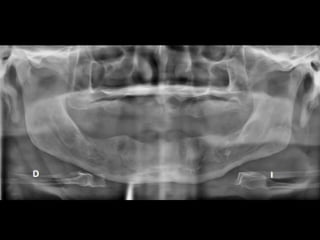

RADIOGRAFÍAS PANORÁMICAS